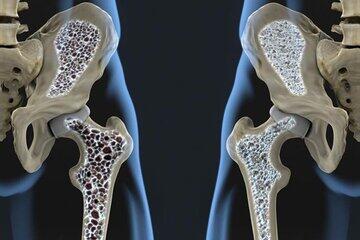

کلسیم ساز ترین میوه

افزایش استحکام استخوانها و مفاصل؛ کلسیم موجود در انجیر خشک تا حد زیادی به افزایش تراکم استخوانها و مفاصل کمک میکند و درصد ابتلاء به پوکی استخوان را به حداقل میرساند.